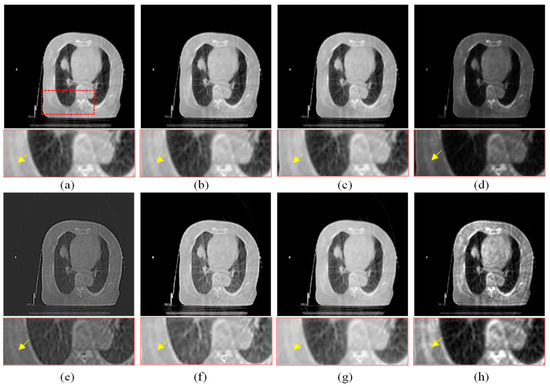

Figure 8.

Enhanced results of pair 2. (a) Source CBCT images. (b) MSR. (c) MSRCR. (d) DCP. (e) CBF. (f) RRM. (g) SMIPC. (h) Ours.

Another three sets of experiments are shown in Figure 8, Figure 9 and Figure 10. As can be seen from the enlarged regions and the yellow arrows in Figure 8, it is difficult to directly observe the presence of skeletal information at this position from the enlarged region in Figure 8a. The enhancement results of the comparison methods also did not improve the visual contrast in this region, but the skeletal information can be clearly observed in our result, which means our results outperform the comparison algorithms in terms of detail, contrast, and visualization effect.

The same conclusion can also be obtained in Figure 9 and Figure 10. Especially in the enalrged region in Figure 10, our results provide a much clearer organizational structural and edge infromation, which is very helpful for disease diagnosis and treatment. Through comparison, it can be found that the rigidity informaiton in our results is more significant, the tissue edge in our results is clearer, and the contrast of the texture structure is also better than that of the comparison algorithms. The observation effect is greatly improved by our enhancement method, proving that our method can effectively enhance the CBCT images.